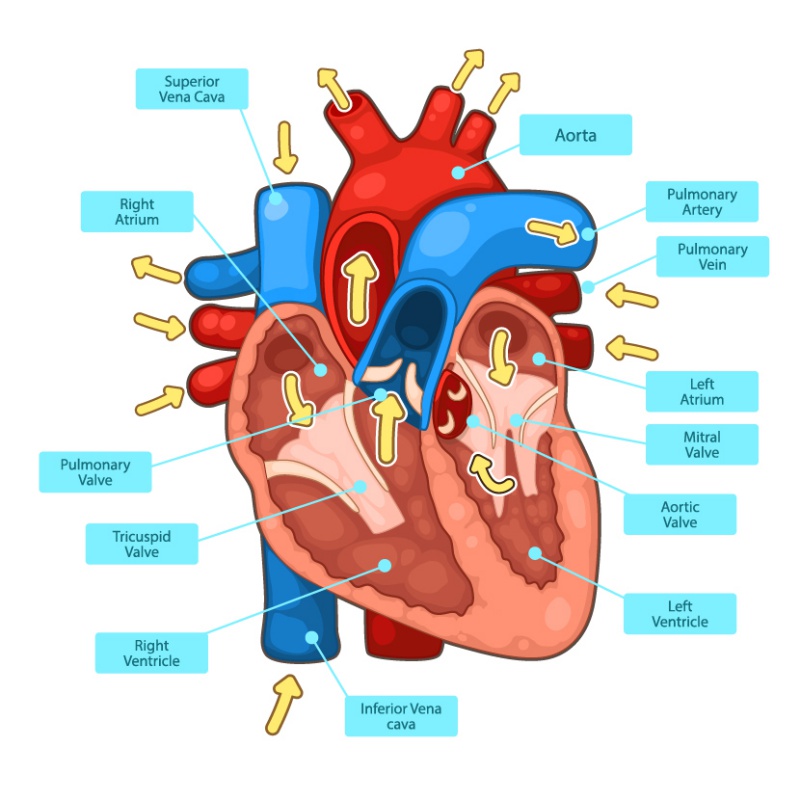

ระบบไหลเวียนโลหิต ทำหน้าที่อะไร และมีส่วนประกอบสำคัญอะไรบ้าง

37,900+ การไหลเวียนของเลือด ภาพถ่ายสต็อก รูปภาพ และภาพปลอดค่าลิขสิทธิ์ … หัวใจกับการไหลเวียนของเลือด – ระบบไหลเวียนโลหิต

ม.2 ระบบหมุนเวียนเลือด | Science – Quizizz ระบบไหลเวียนเลือด: หัวใจ

การไหลเวียนของปอด ภาพประกอบสต็อก – ดาวน์โหลดรูปภาพตอนนี้ – ปอด – ระบบ … Heart Diagram กายวิภาคศาสตร์ร่างกายมนุษย์ระบบไหลเวียนโลหิตหัวใจ …

Heart Diagram กายวิภาคศาสตร์ร่างกายมนุษย์ระบบไหลเวียนโลหิตหัวใจ … ภาพประกอบระบบไหลเวียนโลหิตหัวใจเวกเตอร์ ภาพประกอบสต็อก – ดาวน์โหลดรูป …

แผนภาพแสดงการไหลเวียนของเลือดของหัวใจมนุษย์ ภาพประกอบสต็อก – ดาวน์โหลด … ระบบหัวใจและหลอดเลือด ระบบไหลเวียนโลหิต ภาพประกอบ ภาพสต็อก รูปภาพ และ …

โรคลิ้นหัวใจ – โรงพยาบาลเวชธานี สภาติวเตอร์ By TS Council

ลิ้นหัวใจ หัวใจมนุษย์ ภาพประกอบ ภาพสต็อก รูปภาพ และภาพถ่ายปลอดค่า … Vena Cava Vein ภาพประกอบ กราฟิกแบบเวกเตอร์ปลอดค่าลิขสิทธิ์ และคลิปอาร์ต …

Vena Cava Vein ภาพประกอบ กราฟิกแบบเวกเตอร์ปลอดค่าลิขสิทธิ์ และคลิปอาร์ต … Forme en trois dimensions ภาพถ่ายสต็อก Forme en trois dimensions รูปภาพ …

เข้าใจการทำงานของหัวใจ (Understanding how your Heart Functions) | HD … 280+ Carotid Artery ภาพประกอบ กราฟิกแบบเวกเตอร์ปลอดค่าลิขสิทธิ์ และคลิป …